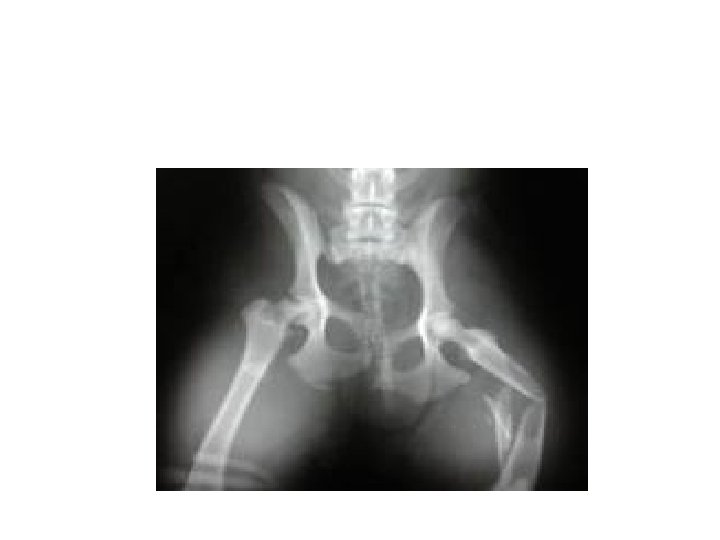

D. Homeostatic Imbalances • Rickets – Lack of vitamin D or calcium during growth – Bowed legs – Deformed pelvis Rickets

B. Male vs. Female Skeleton - Pelvis a. spines farther apart in male b. hole in ischium: smaller and triangular in female c. angle across pubic symphysis = pubic arch: less than 90° and d. distance between more sharply ischia larger in angled in male female